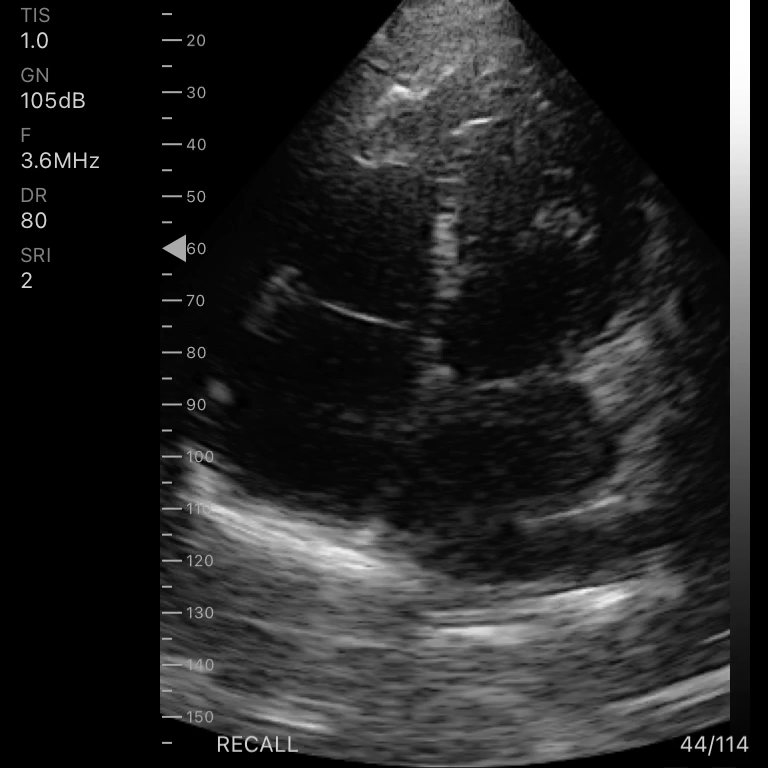

| Modo de escaneo | B, B/M, Color, PW |

Modos de escaneo: B, B/M, Color, PW

Profundidad de pantalla: 90 – 190 mm

Aplicaciones

Emergencias y atención primaria.

Exámenes básicos y control de flujo cardíaco o vascular en entornos clínicos y extrahospitalarios.